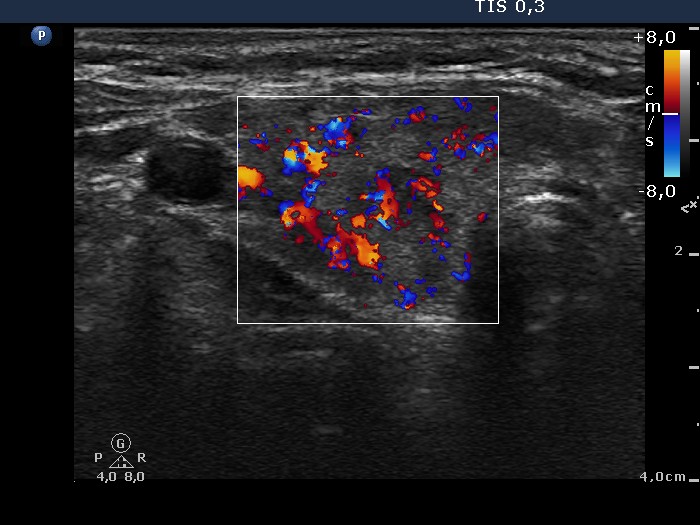

Fourth examination 21 months after initial investigation (fourth and fifth rows):

Clinical presentation: The patient requested a second opinion. Multiple nodules including a suspicious one in the right lobe were described in another institute. Scintigraphy diagnosed multiple "cold" and warm" nodules in both lobes. Surgery was advised. The surgeon asked aspiration cytology of the hypoechogenic nodule described as suspicious on ultrasonography.

Palpation: unchanged.

Results of blood tests: euthyroidism on daily 25 mg methimazole (TSH 3.78 mIU/L, FT4 10.9 pM/L).

Ultrasonography: unchanged.Cytology was performed from the hypoechogenic area in the upper part of the right thyroid.

Cytological diagnosis: benign pattern corresponding to previous dysfunction and isotope therapy.

The patient underwent total thyroidectomy. Histopathology disclosed diffuse goiter corresponding to Graves' disease and focal lymphocytic thyroiditis. There were no nodules.

Comment. It is worth analyzing the echo pattern of the thyroid. The small hypoechogenic area in the right lobe changed neither in size nor is shape nor in vascularization over 11 months.